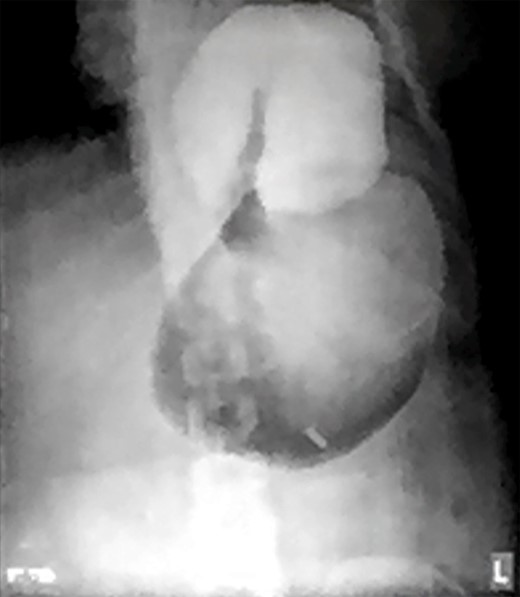

Two days prior to her admission, she had undergone upper gastrointestinal endoscopy for the same complaint in another center that revealed a dilated gastric lumen with herniation of the distal stomach, pylorus and first part of the duodenum into the left hemi-thorax (Fig. 2). She refused treatment and left against medical advice. She presented to our emergency department with worsening symptoms. Resuscitation was commenced with immediate nasogastric decompression, intravenous hydration and analgesia, proton-pump inhibitors and electrolyte replacement. A double contrast-enhanced computed tomography (CT) scan of the chest and the abdomen demonstrated a large diaphragmatic defect (7 × 7 cm) and a left diaphragmatic hernia containing a dilated stomach, suggestive of a gastric outlet obstruction (Fig. 3). A water-soluble gastrografin meal was performed, showing an intra-thoracic, mesentero-axial gastric volvulus (Fig. 4).

Water-soluble gastrografin meal showing an intra-thoracic mesentero-axial volvulus.